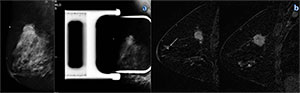

Figure 2. Mammography and MR imaging in a 48-year-old woman with high risk for breast cancer. A: Screening mammogram shows a craniocaudal view of the left breast. B: Mediolateral oblique screening mammogram (left) shows the left breast, and dynamic sagittal MR image (right) of the left breast shows a 1.3-cm index lesion (grade I CDI and grade II DCIS). C: dynamic sagittal MR image shows an additional 1-cm lesion (grade II CLI and grade III DCIS). D: US image shows both lesions and was used to guide biopsy.